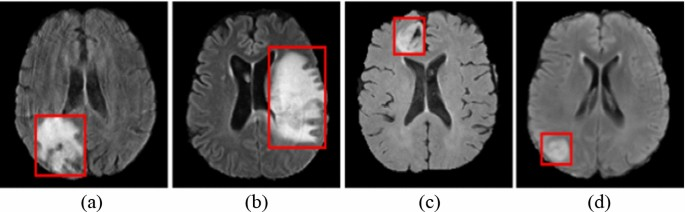

4. Disease Detection and Diagnosis

Generative AI models can aid in the automated detection of abnormalities and pathologies in medical images. By learning from large datasets, these models can identify patterns and features indicative of specific diseases, assisting healthcare professionals in the diagnosis process.